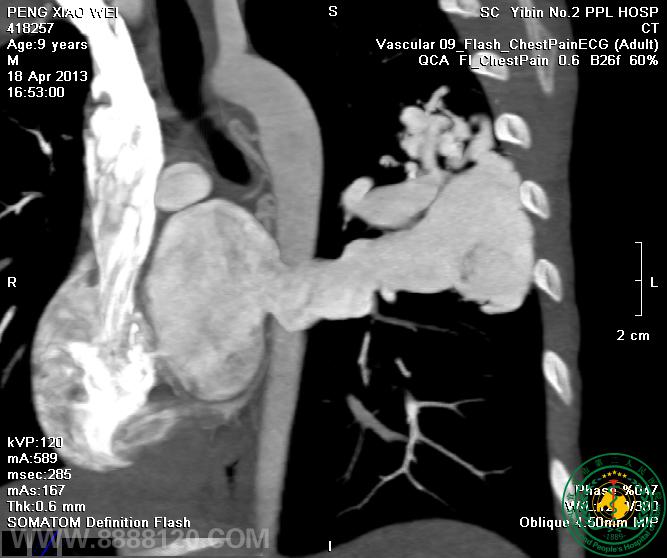

例四:一次扫描显示胸主动脉窦瘤,胸主动脉窦、升主动脉、主动脉弓和降主动脉夹层,破口于主动脉窦,双侧肺血管未见异常(图1-5),左右冠状动脉未见异常(图6)

我院CT室推出胸部血管(冠状动脉、肺动静脉、主动脉)一站式检查技术我院CT室推出胸部血管(冠状动脉、肺动静脉、主动脉)一站式检查技术我院CT室推出胸部血管(冠状动脉、肺动静脉、主动脉)一站式检查技术